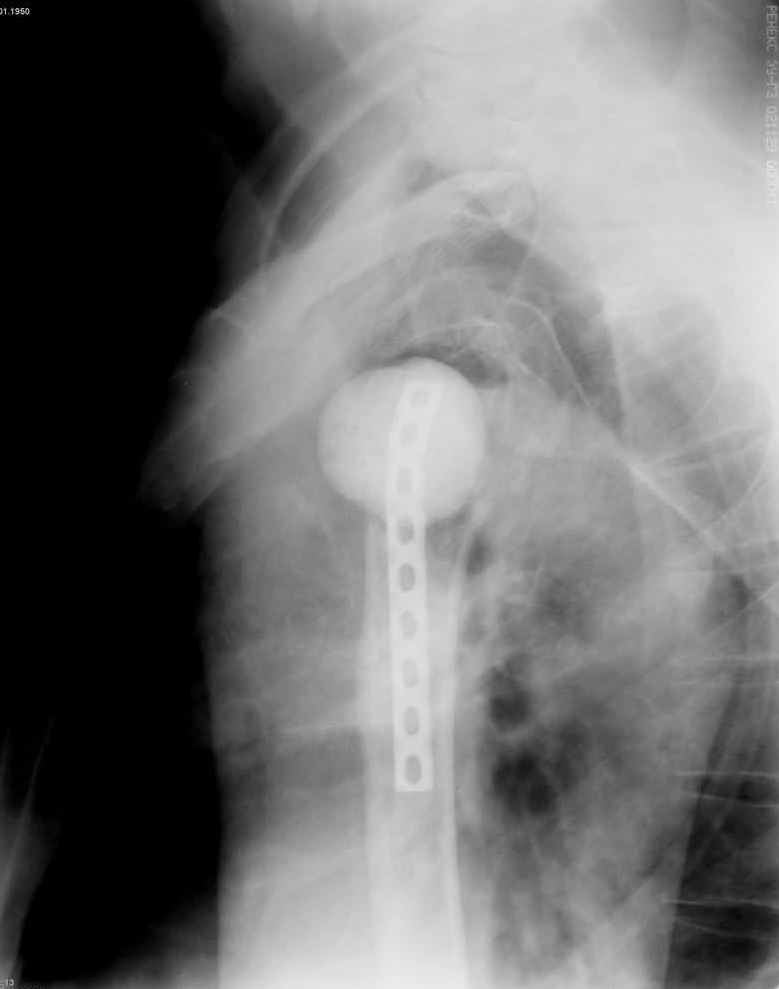

Уважаемые коллеги. Недавно из нашего отделения был выписан пациент 54 лет с закрытым переломом плечевой кости. Из анамнеза: за 2 дня до поступления в НИИСП, в состоянии алкогольного опьянения упал с лестницы на даче (высота 3-4 метра) с упором на правую руку. Через двое суток обратился за медицинской помощью. Доставлен бригадой "Скорой помощи".Правый плечевой сустав умеренно деформирован. По внутренней поверхности плеча имеется кровоподтек. При пальпации плечевого сустава имеется умеренная болезненность. Активные и пассивные движения болезненные. Снижена чувствительность по тыльной поверхности пальцев кисти и отсутствует активное разгибание кисти и пальцев. Имеется подкожная эмфизема шеи, верхней половины грудной клетки (рис 1, 2). На рентгенограмме: оскольчатый перелом головки плечевой кости со значительным смещением, перелом 2-3 ребер справа, тканевая эмфизема (рис 3). КТ при поступлении: перелом головки плечевой кости в области анатомической шейки со смещением отломка головки в грудную полость, правосторонний гидроторакс, перелом 2-3-4 ребер справа. (рис 4). Через двое суток после поступления выполнена операция: атипичная торакотомия, эвакуация свернувшегося гемоторакса, удаление инородного тела (головки плечевой кости) из плевральной полости (при этом выявлено имеющееся повреждение париетального и висцерального листков плевры) (рис. 5), дренирование плевральной полости, замещение проксимального конца плечевой кости спейсером из костного цемента с антибиотиком (рис. 6). Послеоперационный период протекал гладко. При контрольной рентгенографии положение спейсера удовлетворительное (рис. 7, 8). Дренаж из плевральной полости удален через 3 суток после вмешательства. Послеоперационная рана зажила первичным натяжением. Через 12 дней после операции больной выписан на амбулаторное лечение.

Я абсолютно согласен с Вами. Бугорки мы не выделяли и не фиксировали. Дело в том, что основная линия перелома проходит по анатомической шейке. И ниже нее кость повреждена, но существенного смещения осколков и бугорков до и во время операции не отмечено (прилагаю первичный снимок лучшего качества - рис. 1).